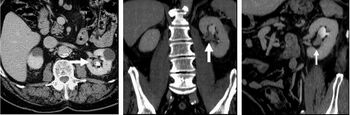

CT angiography (CTA) is highly effective for evaluation of the arterial system, and has largely replaced conventional angiography due to the lower risk profile and ability to survey the entire abdomen. Images are acquired after a rapid bolus of intravenous contrast material (3-7 cc/s) during the arterial phase (15–35 seconds after injection) when the concentration of contrast material in the arterial system is high (figures 3). Images are usually acquired using narrow collimation (<1 mm) and can be retrospectively reconstructed using dedicated 3-dimensional workstations and software. CTA is commonly used in the head and chest in the evaluation of pulmonary emboli, aneurysms, vascular malformations, dissection, bleeding and ischemia. Indications for early arterial phase imaging include: evaluation of aneurysms or dissections (cerebral, aortic, etc.), hepatic, splanchnic or renal arterial anatomy, and arterial imaging in liver or kidney transplantation. Single phase arterial imaging is often used in the evaluation of trauma patients either a complete chest/abdomen/pelvis examination with arterial phase imaging of the chest and portal venous phase imaging of the abdomen/pelvis or just a portal venous phase of abdomen and pelvis depending on the mechanism and severity of the trauma. CTA is also commonly performed in the abdomen and pelvis for evaluating vascular malformations and in the evaluation of bleeding. Mesenteric ischemia can also be evaluated using CT angiography. CTA of the abdomen and pelvis is often performed in combination with a CTA for evaluating the extremity vasculature.[citation needed]

The late arterial phase is timed to correspond to the peak concentration of contrast material in highly vascular tumors and is performed approximately 20–35 seconds after the injection of intravenous contrast. Early arterial phase imaging is predominantly utilized for angiography and will be discussed separately. Late arterial phase imaging is almost always performed in conjunction with other phases (e.g. portal venous phase) to allow more complete characterization of any identified abnormalities (figure 4). The primary indication for a late arterial phase is for the evaluation of hypervascular tumors of the liver such as hepatocellular carcinoma or hypervascular metastases (figure 4). Typical hypervascular tumors for which this would be used include: hepatocellular carcinoma; renal cell carcinoma; melanoma; carcinoid/neuroendocrine tumors; some sarcomas; choriocarcinoma; and thyroid carcinoma. Although a “hypervascular”, biphasic evaluation would generally be used for these patients, note that a single phase is often adequate for follow up imaging.[citation needed]